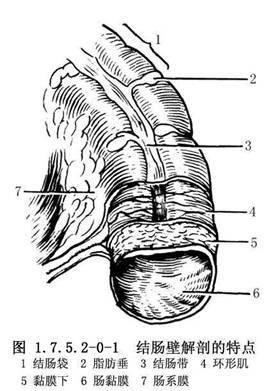

結腸長約1.5m,約爲小腸的1/4。結腸外觀上有4個特徵,易與小腸鑑別:①結腸帶:是結腸壁縱肌層集聚而成的3條縱帶,自盲腸端至乙狀結腸直腸交界處;②結腸袋:因結腸帶較短而結腸較長,引起腸壁皺縮成囊狀;③脂肪垂(腸脂垂):是結腸的髒層腹膜下脂肪組織集聚而成,沿結腸帶分佈最多,在近端結腸較扁平,在乙狀結腸則多呈帶蒂狀;④腸腔較大,腸壁較薄(圖1.7.5.2-0-1)。結腸分爲盲腸、升結腸、橫結腸及乙狀結腸等。結腸的功能主要是吸收水分和儲存糞便(圖1.7.5.2-0-2)。吸收作用以右半結腸爲主,因其內容物爲液體、半液體及軟塊樣,故主要吸收水分、無機鹽、氣體、少量的糖和其他水溶性物質,但不能吸收蛋白質與脂肪。若右半結腸蠕動降低,則加強吸收能力;橫結腸內若有硬的糞塊,常導致便祕。左半結腸的內容物爲軟塊、半軟塊或固體樣,故僅能吸收少量的水分、鹽和糖。若左半結腸腸蠕動增強,則降低吸收能力,常有腹瀉或稀便。結腸黏膜僅能分泌黏液,使黏膜潤滑,以利糞便通過。切除結腸後,吸收水分的功能逐漸由迴腸所代替,故主要對切除結腸的任何部分,甚至全部,也不致造成永久性代謝障礙。